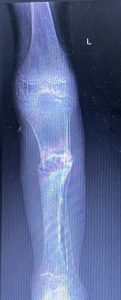

Bei der 3jährigen Chantal (Name geändert) hatten die ruandischen Kollegen einen riesigen Sequester aus der Tibia (Schienbein) entfernt. Nach Abklingen aller Infektzeichen bestand nun die Indikation den entstandenen Defekt mit einem Fibulatransplantat zu überbrücken.

Beim dreijährigen Jean (Name geändert) bestand die Indikation für eine Sequestrektomie und eine Abszessentlastung, die morgen von Dr. Jean d‘ Amour mit Hilfe der beiden deutschen Unfallchirurgen durchgeführt werden.

Dr. Feltes und Dr. Weber hatten für heute geplant die kleine Chantal (Name geändert) zu operieren. Geplant war den Tibiadefekt rechts mit einem Fibulatransfer zu decken. So gegen 13 Uhr wurden die beiden in den OP gerufen.

Das war die Ausgangssituation.

Und dies das Ergebnis nach 2-stündiger Operation.

Die beiden Ärzte gehen auf Station und visitieren die beiden kleinen Patienten, die sie operiert hatten. Anschließend gingen sie in die Röntgenabteilung um zu checken, ob die Kinder bereits postoperativ geröntgt wurden. Da dies noch nicht der Fall war, wurden aber Röntgenkontrollen jetzt angeordnet. Danach ging’s ins Labor. Aber dort konnte mach noch kein gesichertes Ergebnis der beiden Abstriche aus der Tibia von Jean bekannt geben. Sobald das Ergebnis vorlag, hat Diana den beiden Ärzten Bescheid gesagt: Das bereits verordnete Antibiotikum konnte weiter verabreicht werden, da die festgestellten Bakterien sensibel darauf reagierten. Das ist schon ein bedeutender Fortschritt in der Antibiotikatherapie am Kibogora Hospital.